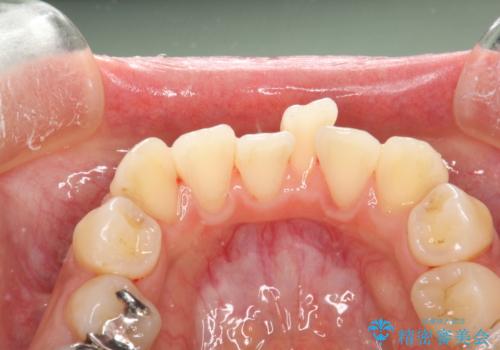

- 矯正前にしっかりとクリーニングを行いたいとのことで来院されました。PMTC30分コースを行いました。

プラーク(細菌の塊)や歯石がたまると歯の表面はザラつきいてきます。そのザラつきは歯周病や虫歯菌の棲家となります。そのまま放置すると、歯肉が腫れてきたり、歯肉から出血したり、口臭が強くでたりします。とくに歯肉の境目は、歯磨きで汚れを除去することが難しく、プラーク(細菌の塊)や歯石が溜まりやすい場所です。

歯並が、がたついている場合はなおさら汚れが溜まりやすいです。矯正治療前や定期的にPMTCをすることで、矯正治療中の歯肉トラブルを防ぐことにつながります。